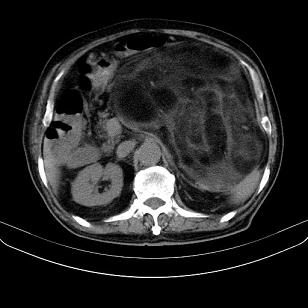

标题: CT21671:男,88岁,左上腹包块 [打印本页]

标题: CT21671:男,88岁,左上腹包块

患者因咳嗽而住院,自觉右上腹包块,无其他不适。

腹膜后高分化脂肪肉瘤

腹膜后脂肪肉瘤

腹膜生占位性病变,脂肪肉瘤可能。

左侧腹膜后脂肪肉瘤。